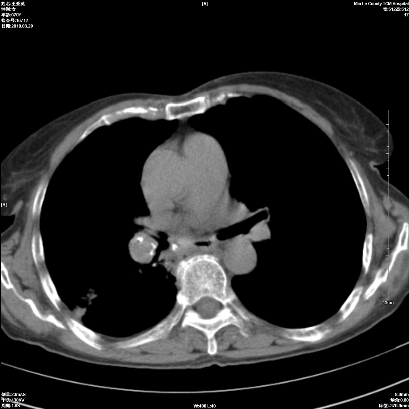

右肺上叶支气管开口阻塞,上叶呈不均匀致密影,右肺中下叶内见斑片状密度增高影,上叶见钙化点,纵隔内见钙化淋巴结,桶状胸,右下肺动脉增粗,残根征,意见:1.右肺中心性肺癌;2.右肺陈旧性结核;3.肺心病。

ct所见:右肺上叶肺不张,呈软组织密度影向肺门区聚拢,其内可见含气段支气管及细支气管影,病灶内尚可见钙化结节。右肺上叶支气管狭窄,段支气管壁可见钙化。右肺下叶背段、右肺中叶见不规则小片絮状影及纤维条索影,形态较僵硬。右肺中叶胸膜旁可见多个小结节影。纵膈内见钙化淋巴结。

分析:右侧胸廓及右肺体积缩小,说明病变时间比较长了,应该是有数年的时间了,如果是短期内出现的肺不张,只会引起纵膈向患侧移位,而不会引起胸廓的塌陷。不张的肺组织内可见含气支气管影,说明右肺上叶支气管没有完全中断,只是狭窄。右肺中叶、下叶散在不规则病灶,部分呈纤维化改变。纵膈内的淋巴结大部分钙化。因此,本例给我的感觉良性病变的可能是大。

结论:考虑右肺上叶支气管内膜结核合并右肺上叶肺不张;右肺中叶、下叶陈旧性肺结核改变。